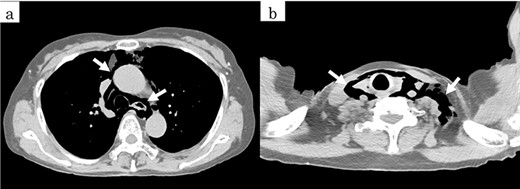

On chest and abdominal CT, free gas was observed in the entire abdominal cavity (Fig. 1a), and extensive emphysema was also observed in the retroperitoneum (Fig. 1b). In addition, it was observed from the mediastinum to both sides of the necks (Fig. 2).

Postoperatively, the patient was withdrawn from the ventilator on hospital Day 1. Chest and abdominal CT performed on hospital Day 8 confirmed a marked reduction in emphysema from the retroperitoneum to the mediastinum and neck (Fig. 5). The patient’s postoperative course was good, and she was discharged on hospital Day 21.

Postoperative CT showed a decrease of the pneumoretroperitoneum and pneumomediastinum (arrows).